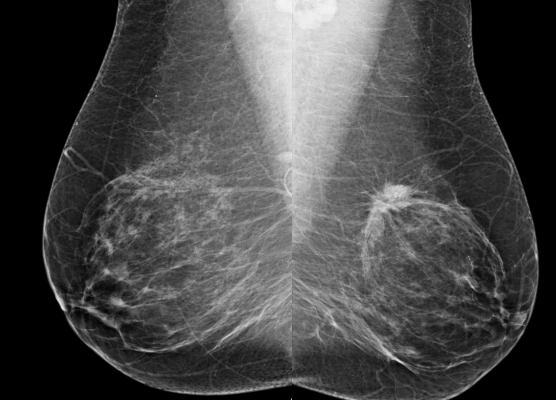

Patient 1: Bilateral MLO views from screening mammography in a 53-year-old woman.